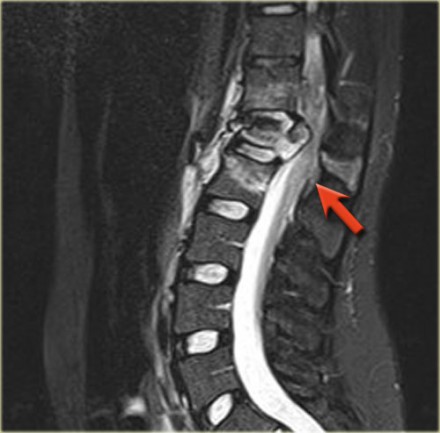

Look at the images.

What are the findings?

The findings are:

- Vertebral bodies show marrow edema as a result of a fracture.

- Torn flaval ligament (yellow arrow).

- Fractures through the posterior elements (red arrows).

The TLICS-score is high, because there is distraction and injury to the PLC.